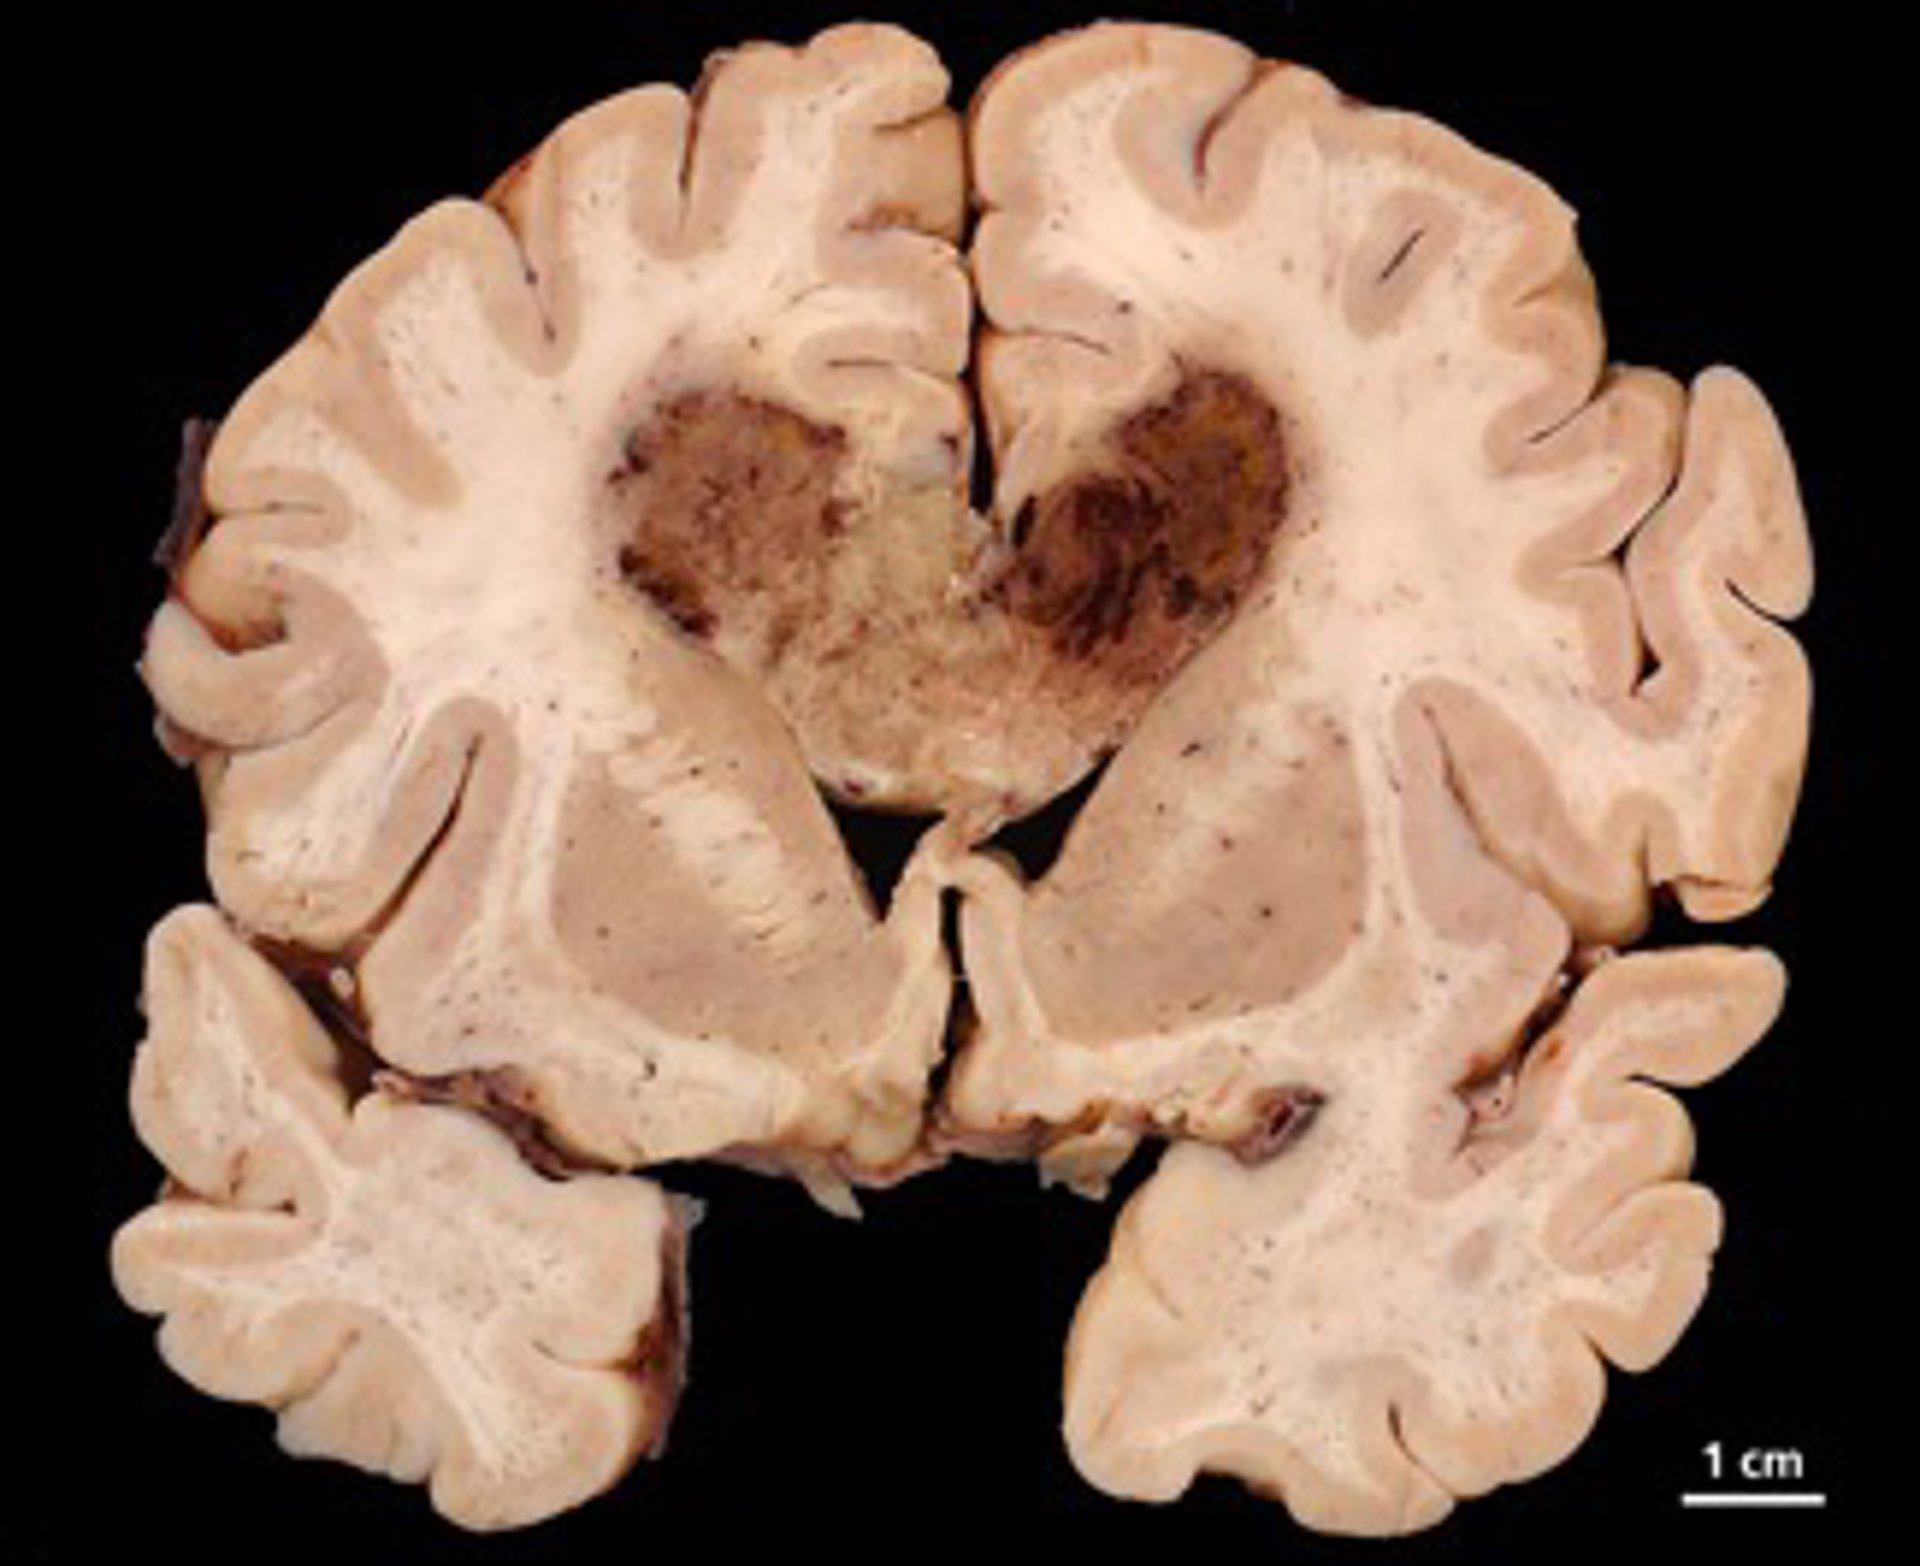

Archivo - Glioblastoma

Archivo - Glioblastoma - UC SAN DIEGO SCHOOL OF MEDICINE - Archivo